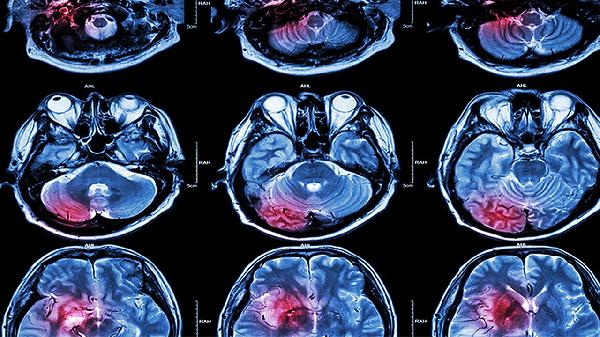

脑外伤的病因有哪些 这些原因会导致脑外伤

脑外伤可能由交通事故、高处坠落、暴力击打、运动损伤及职业暴露等原因引起。1、交通事故: 机动车碰撞、行人被撞击等交通意外是脑外伤的首要病因。高速冲击易导致颅骨骨折或脑组织挫裂伤,摩托车事故中未佩戴头

脑梗神经疼怎么缓解

脑梗通常是指脑梗死。患有脑梗死后出现神经疼痛,可以在医生指导下通过调整作息时间、降低颅压、调理神经等方法辅助改善症状。具体介绍如下: 1、调整作息时间:患有脑梗死,说明颅脑组织细胞局部血管存在血液流

脑干出血神经损坏了还能恢复正常吗

脑干出血引起的神经损坏通常难以完全恢复。 脑干出血对神经细胞造成急性损伤,可能导致永久性神经功能缺损。尽管在出血吸收过程中可能出现部分功能恢复,但由于脑干结构复杂且涉及多种生命维持功能,因此完全康复